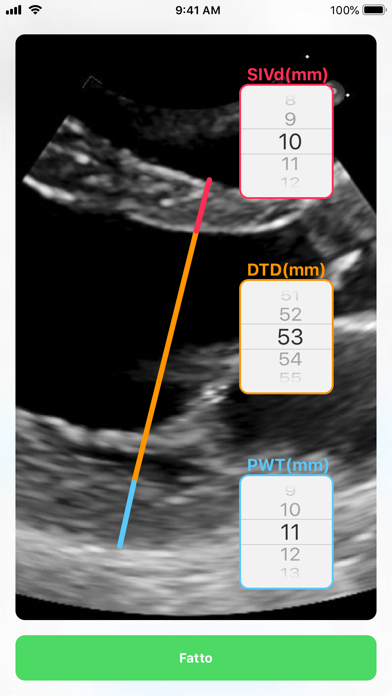

Con l’esame ecocardiografico è possibile stimare la massa del ventricolo sinistro e determinare lo spessore relative delle pareti.

L' app consente in tempo reale di determinare il pattern di geometria del ventricolo sinistro.

• Screenshot #2 pour LVG Calc

• Screenshot #3 pour LVG Calc